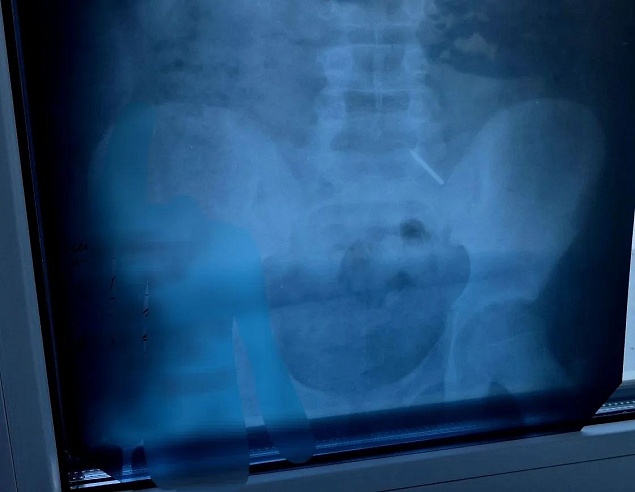

Как рассказала детский хирург Дарья Гусева, из-за позднего обращения за помощью достать предмет с помощью эндоскопа не удалось. Основной задачей врачей стало предотвратить повреждение кишечника и внутреннее кровотечение. Ребенка тщательно наблюдали, делали контрольные рентгеновские снимки.

Фото: Балаковская городская клиническая больница